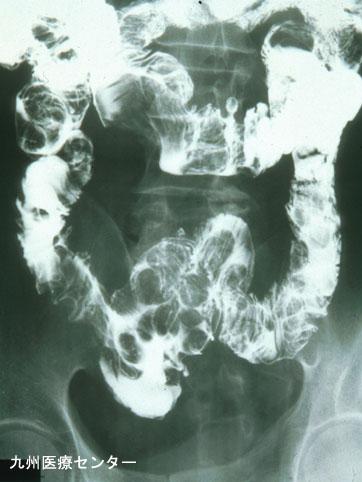

다발성게실을 동반한 다발성의 소장 지방종증 (증례제시:국립병원 큐슈우 의료센터)

[Image-ID:3044]

양성 비상피성종양/지방종

소장/2개 이상

X-P

15~19